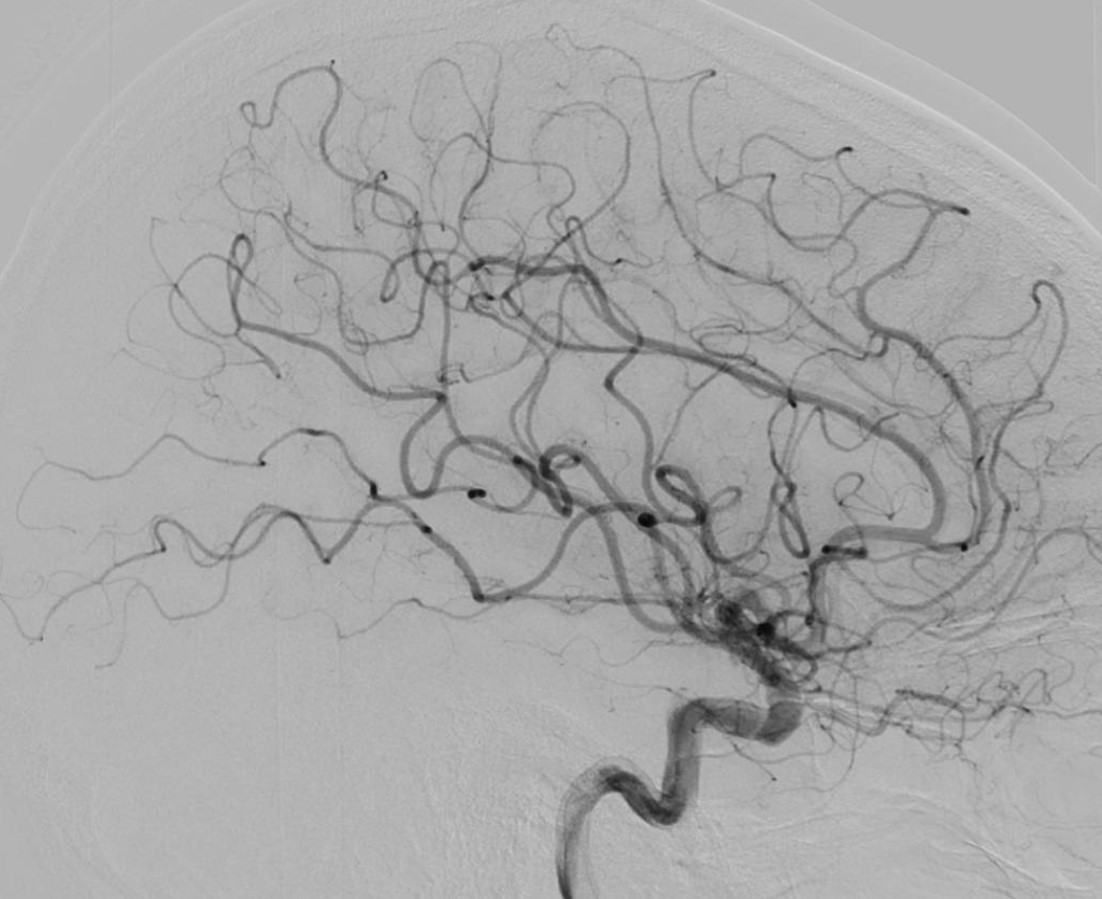

L’artériographie cérébrale, ou angiographie cérébrale, est une technique d’imagerie médicale diagnostique invasive qui permet de visualiser les vaisseaux sanguins du cerveau. Elle consiste à injecter un produit de contraste iodé directement dans les artères, via un cathéter (petit tuyau), ce qui rend les vaisseaux visibles par les systèmes d’imagerie à rayons X. Cette procédure est réalisée par un neuroradiologue interventionnel et permet d’obtenir des images très détaillées du réseau vasculaire cérébral.

L’artériographie cérébrale est utilisée pour diagnostiquer des pathologies vasculaires, tels que les anévrismes intracrâniens, les malformations ou fistules artério-veineuses, les vascularites et les sténoses artérielles. Il s’agit d’un acte interventionnel à visée diagnostique. L’extrême précision des images permet aux médecins de comprendre en détail et en 3D l’état vasculaire du patient et de décider des meilleures options de traitement.

L’artériographie cérébrale est la méthode la plus précise et l’examen de référence pour diagnostiquer les pathologies des vaisseaux sanguins du cerveau. Elle permet un diagnostic détaillé des affections vasculaires cérébrales, bien plus fin que d’autres techniques d’imagerie comme l’IRM ou le scanner. Grâce à sa haute résolution spatiale, elle est particulièrement efficace pour guider les traitements, comme l’embolisation d’un anévrisme.